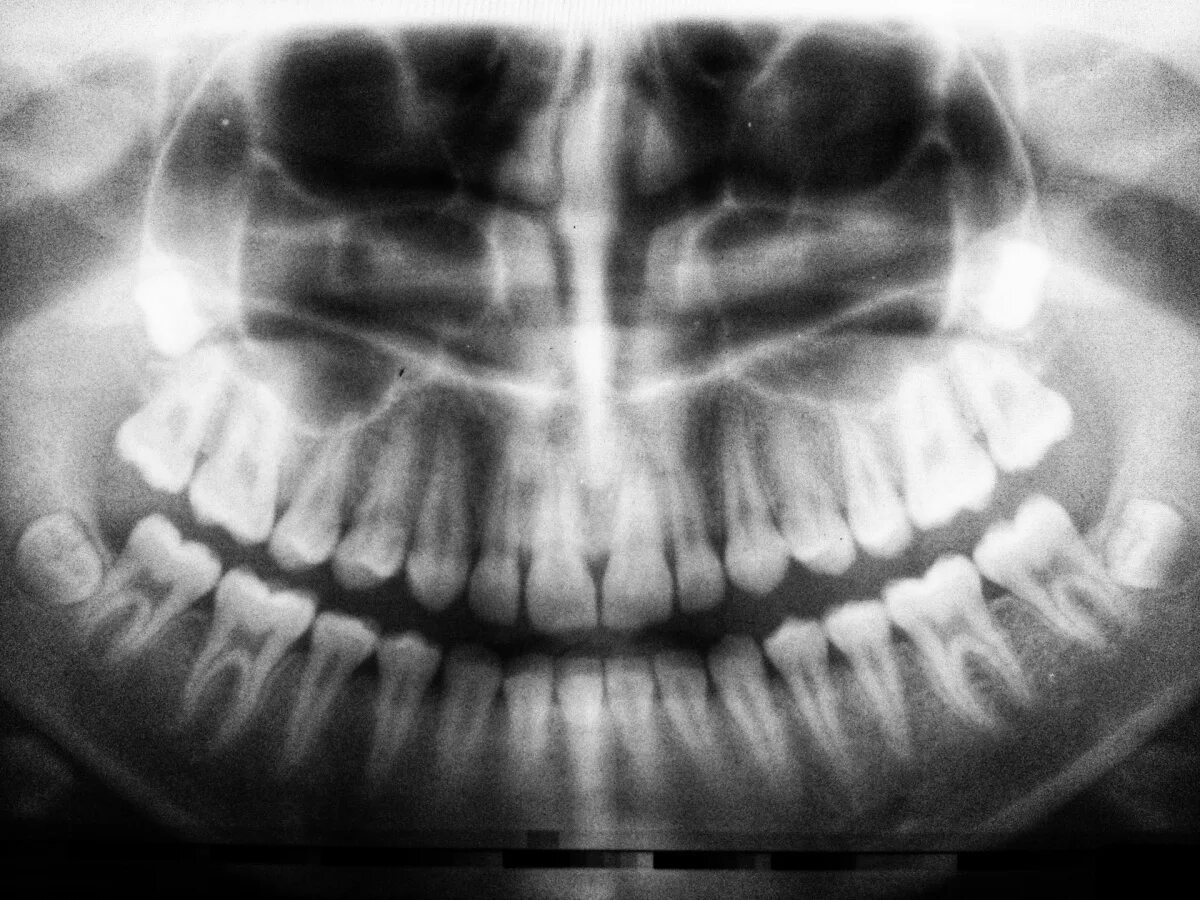

Снимок ротовой полости